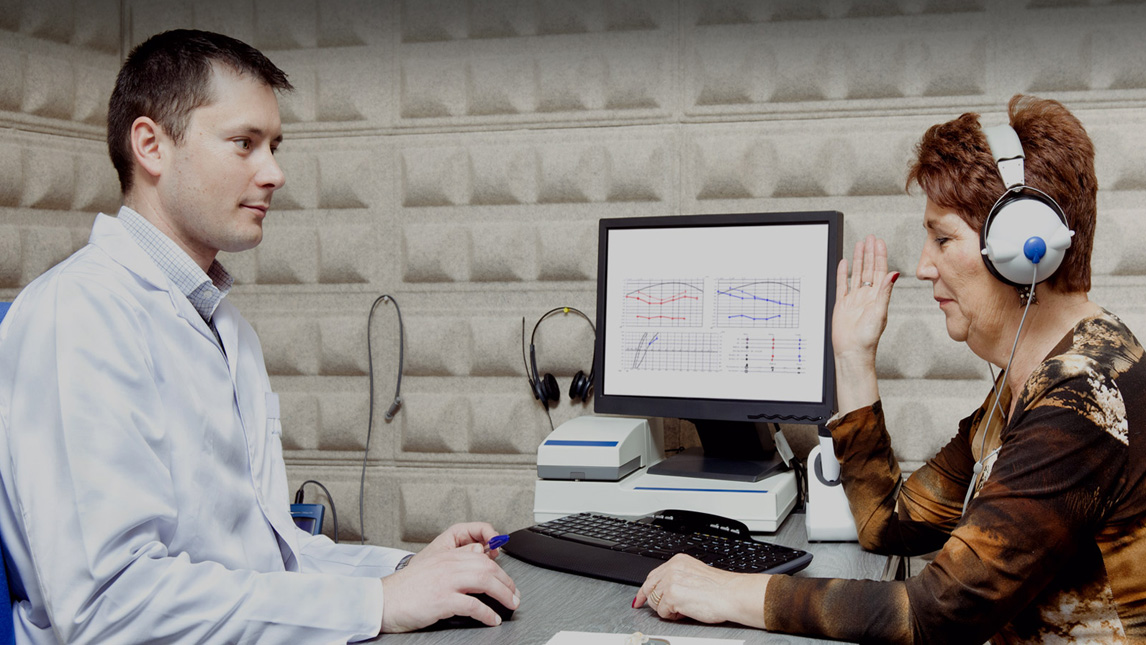

Deafness is one of the most common sensory deficits. The Auditory Laboratory specialises in original research into the physiology of hearing, deafness and tinnitus, and associated aspects of neurophysiology and membrane transport. It is one of Australia's leading research institutions in auditory physiology, and hosts UWA’s Master of Clinical Audiology.

The Auditory Laboratory researches the physiology of hearing, including deafness, tinnitus and forms of auditory plasticity. The laboratory is one of Australia's leading research institutions in auditory physiology, and has established a worldwide reputation for excellence in teaching and research. The laboratory also hosts the Master of Clinical Audiology and the Master of Clinical Audiology and Doctor of Philosophy.

- Behavioural testing

- Cochlear physiology

- Histology

- In vitro preparations

- Molecular biology

- Neuronal electrophysiology in vivo

- Otoacoustic emissions